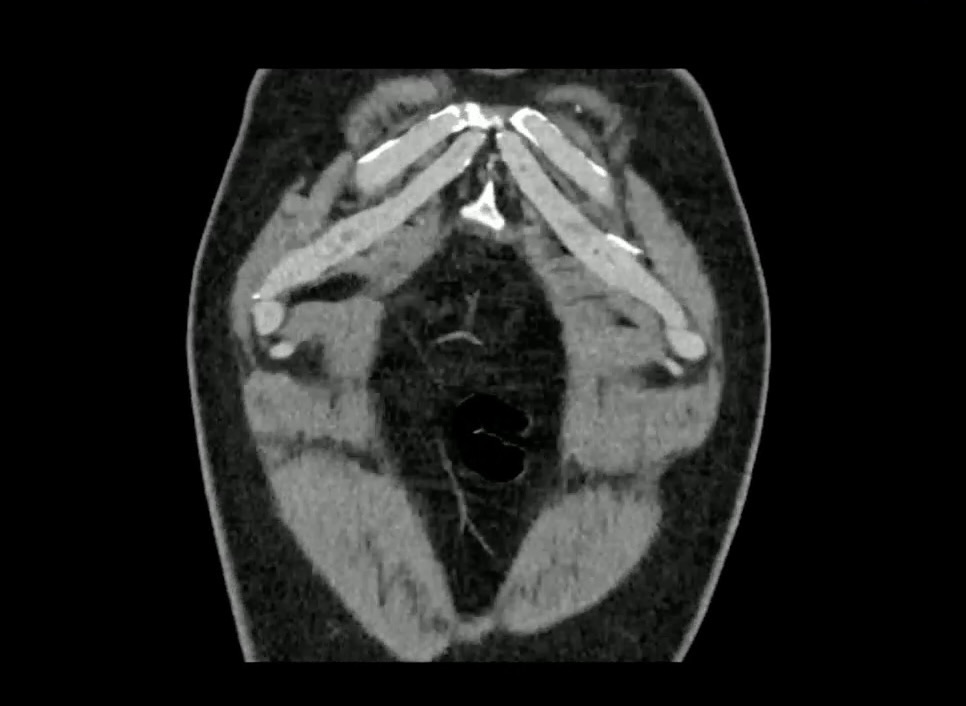

【患者信息】:男,60岁。

【主诉】:间断上腹部疼痛30天。

十二指肠溃疡 (97)